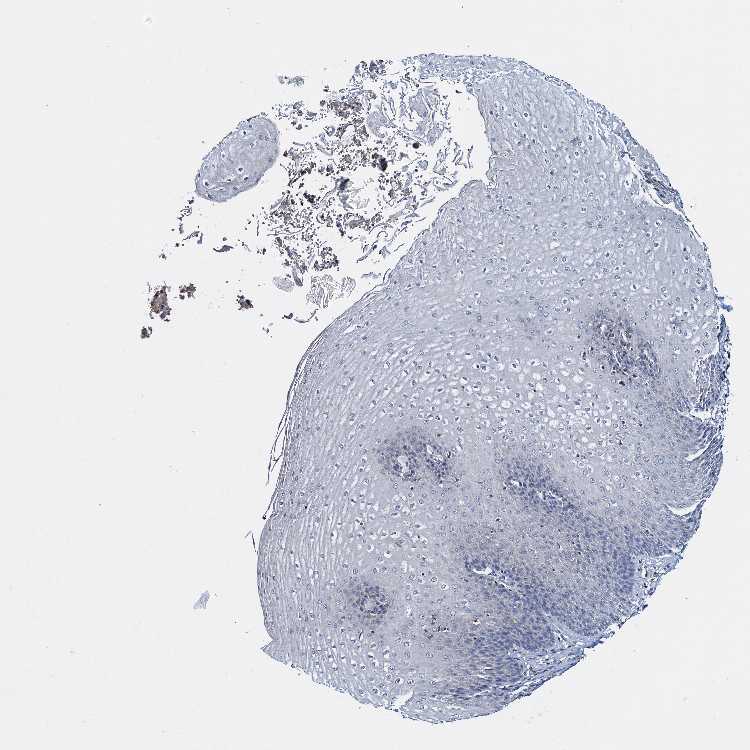

ESOPHAGUS - Antibody stainingi

Antibody staining in the annotated cell types in the current human tissue is reported as not detected, low, medium, or high, based on conventional immunohistochemistry profiling in selected tissues. This score is based on the combination of the staining intensity and fraction of stained cells.

Each image is clickable and will lead to virtual microscopy that enables deeper exploration of all samples and also displays staining intensity scores, fraction scores and subcellular localization as well as patient and tissue information for each sample.

Antibody HPA039827

Squamous epithelial cells Not detected